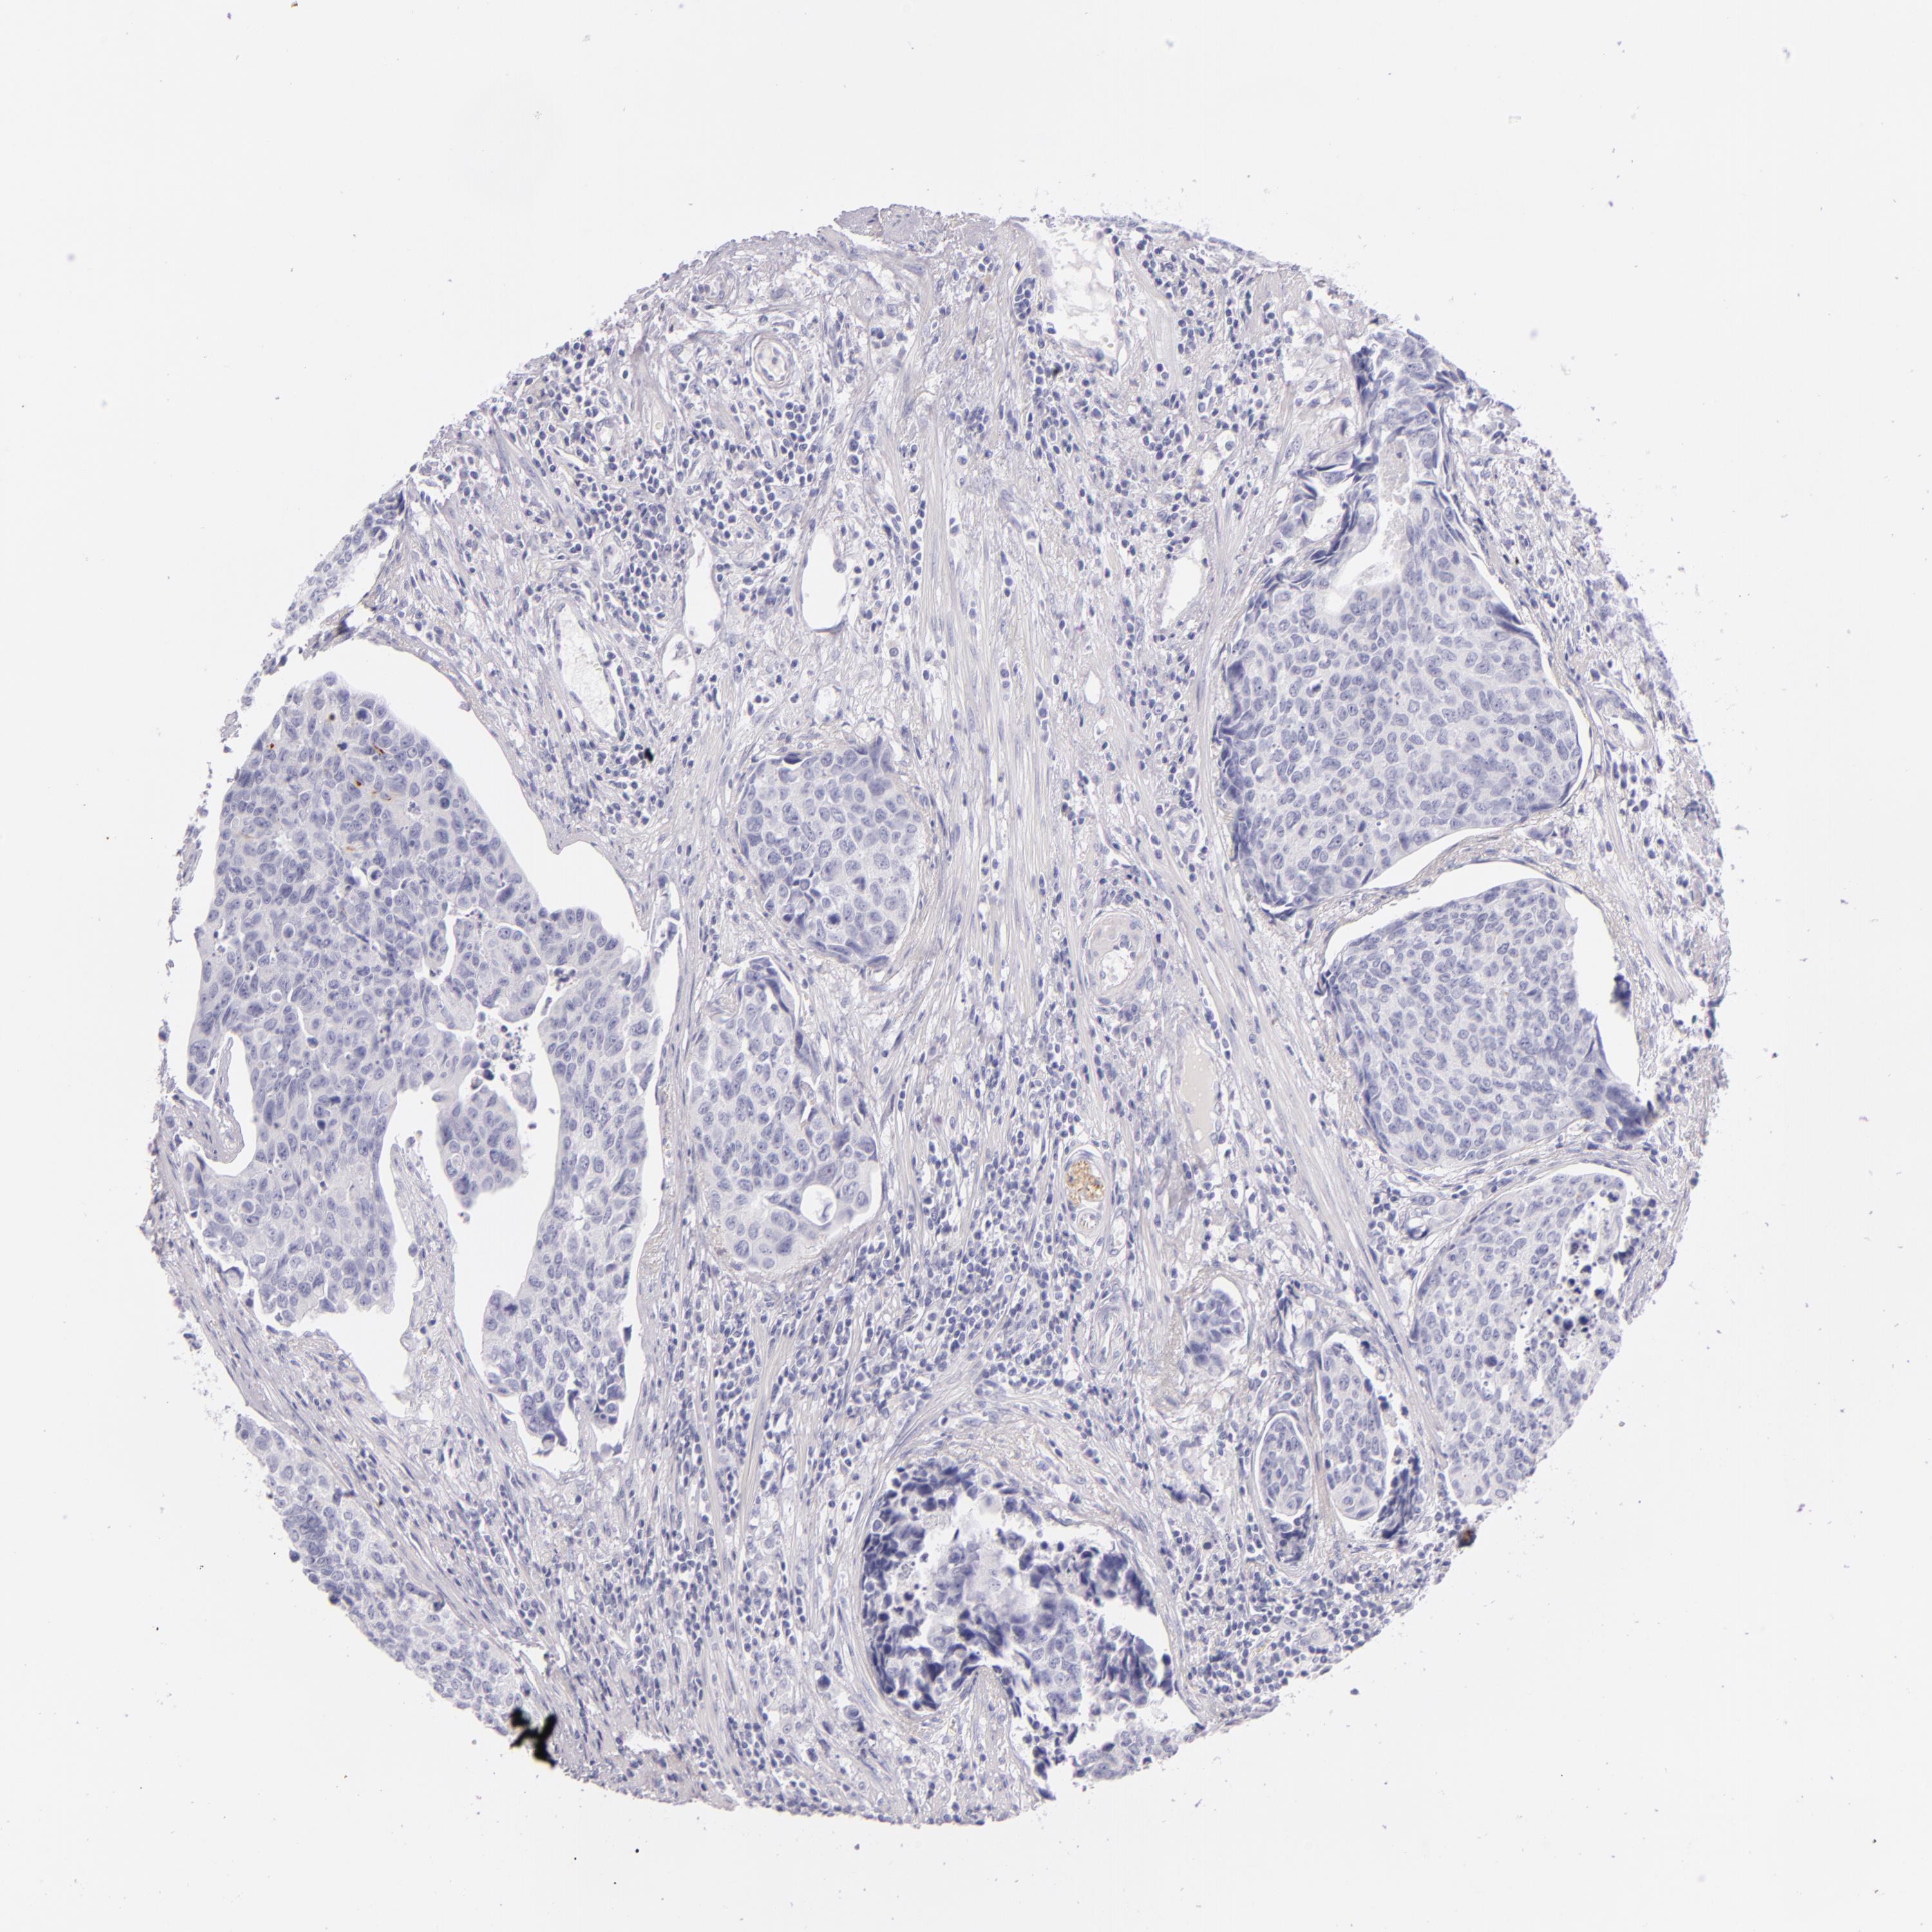

UROTHELIAL CANCER - Protein expressioni

A mouse-over function shows sample information and annotation data. Click on an image to view it in a full screen mode. Samples can be filtered based on level of antibody staining by selecting one or several of the following categories: high, medium, low and not detected. The assay and annotation is described here.

Note that samples used for immunohistochemistry by the Human Protein Atlas do not correspond to samples in the TCGA dataset.

Antibody stainingi

Antibody staining in the annotated cell types in the current human tissue is reported as not detected, low, medium, or high, based on conventional immunohistochemistry profiling in selected tissues. This score is based on the combination of the staining intensity and fraction of stained cells.

Each image is clickable and will lead to virtual microscopy that enables deeper exploration of all samples and also displays staining intensity scores, fraction scores and subcellular localization as well as patient and tissue information for each sample.

Antibody HPA008057

Antibody CAB002059

Urothelial carcinoma, High grade

Urothelial carcinoma, NOS

Urothelial carcinoma, Low grade

Adenocarcinoma, NOS